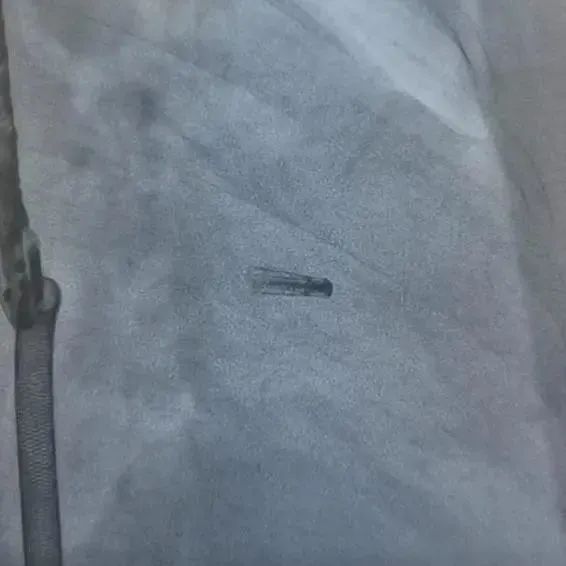

▲术前超声心动图(二尖瓣反流4+)